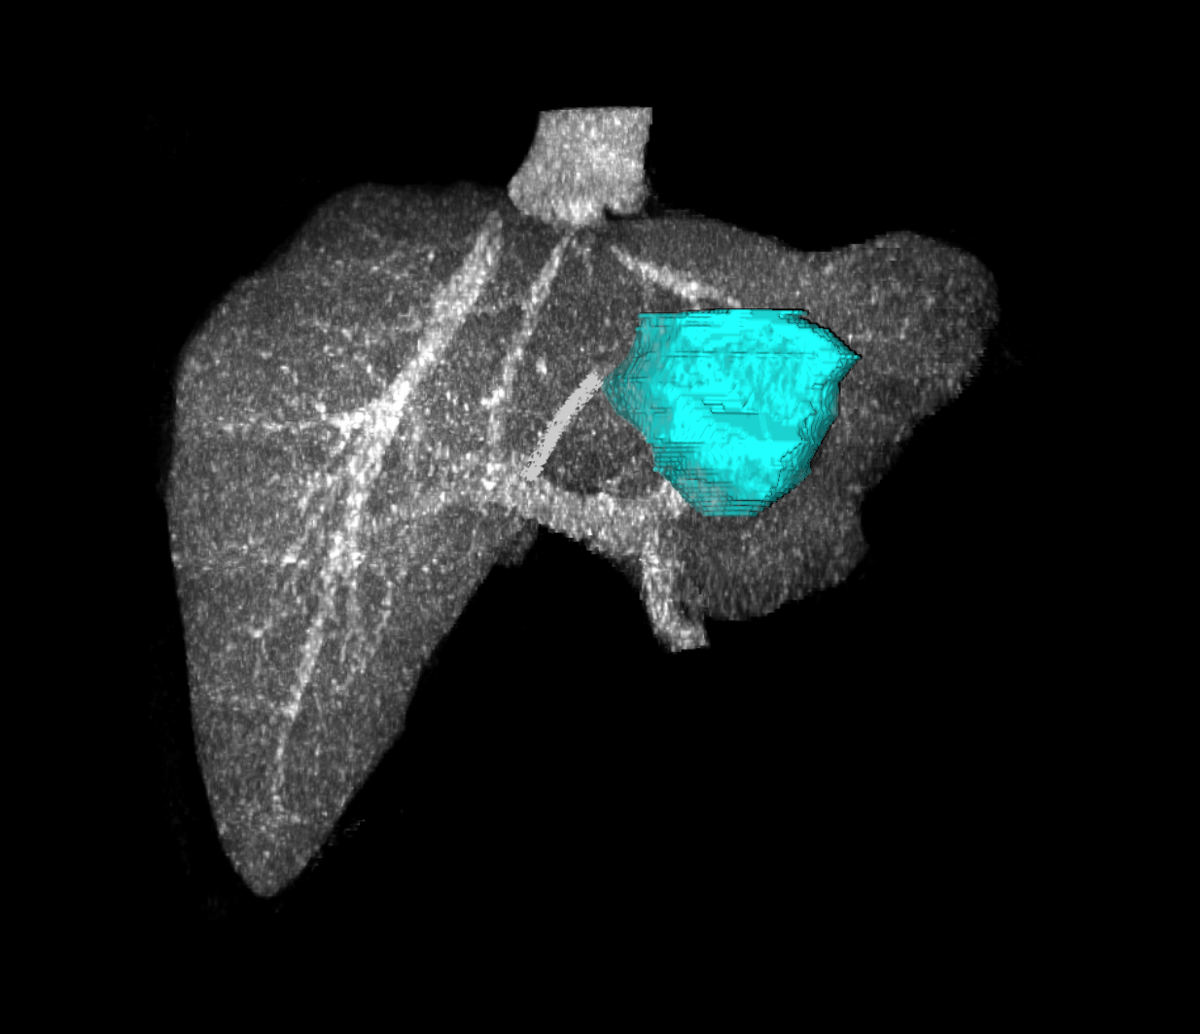

Early diagnosis of a hepatoma (also called primary liver cancer, hepatocellular cancer, or HCC) gives the best chance of long term survival. Patients needing routine liver cancer surveillance are: 1) all patients with cirrhosis, and 2) patients with hepatitis B infection and detectable virus growing in their blood. The most common causes of cirrhosis in the United States are hepatitis C and/or B infection, alcohol over use, and fatty liver. Unfortunately, 7 out of 10 patients with liver cancer have advanced cancer when found and will not benefit from surgical removal or liver transplant.

The most common cancer to the liver is metastatic from the colon or rectum. Surgical removal of cancer in the liver from the colon or rectum gives patients a 30-35% chance of being alive 5 years after surgery. Without surgery, most patients die within 12-18 months after diagnosis. Predictors of outcome include tumor size greater than 5 centimeters, having more than one tumor, having positive lymph nodes at the initial colorectal surgery, having a CEA greater than 200, and time between original colorectal surgery and development of metastatic tumor in liver less than 1 year. A patient without any of these risk factors has about a 7 out of 10 chance of being alive in 5 years. As a patient has more risk factors, their chance of surviving decreases. If a patient has all 5 risk factors, they have a 1 out of 10 chance of being alive in 5 years.